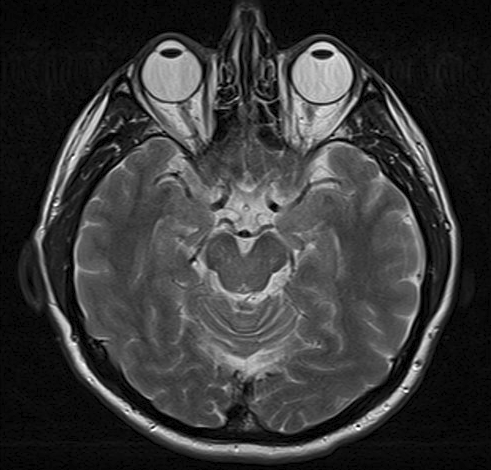

This image is an MRI scan of a brain. The person's eyeballs can be seen at the top of the picture.

MRI scan

By Ptrump (Own work) via Wikimedia Commons